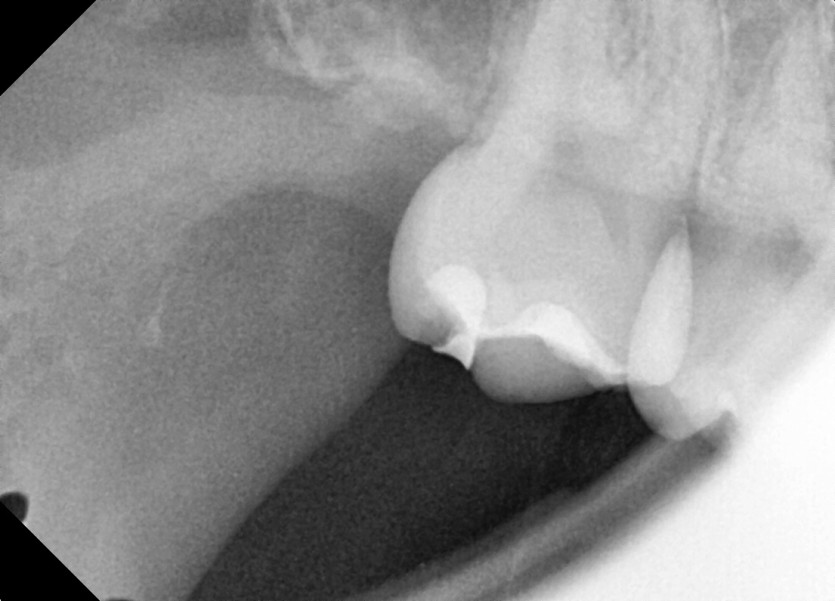

#18,48 사랑니 발치

구강 외과 전문의가 당일 발치했습니다.